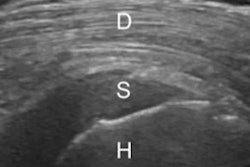

To address the problem, Berko and colleagues designed a peer-led musculoskeletal ultrasound curriculum with a hands-on scanning component for radiology residents. The curriculum consisted of five one-hour lectures and two hands-on workshops. Study participants included 37 residents and six radiologists who served as peer teachers, four of whom were fourth-year residents and two of whom were musculoskeletal radiology fellows.

The researchers assessed the residents' diagnostic ultrasound skills via a multiple-choice test before and after the curriculum was administered; their hands-on skills were evaluated at the end of the course and two months later. The residents also gauged their own confidence in performing musculoskeletal ultrasound both before and after the course via a survey based on a five-point scale (with 1 meaning "strongly disagree" or "no knowledge" and 5 meaning "strongly agree" or "comprehensive knowledge").

At the end of the workshops, participants were able to obtain diagnostic-quality ultrasound images 100% of the time; however, two months later, they were able to do this 79% of the time -- a drop the researchers attributed to a lack of continued practice.